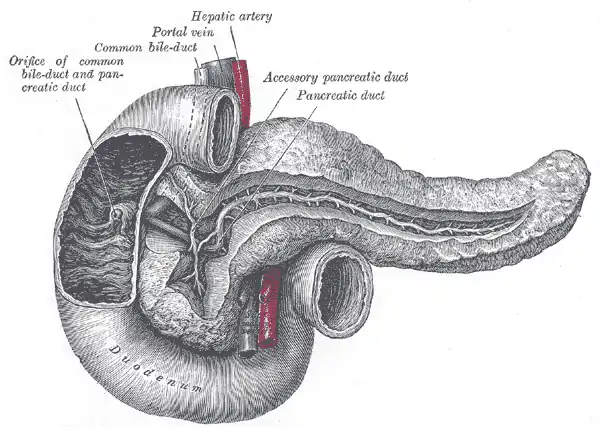

Biliary System & Pancreas

Bile and bile salts are manufactured by the liver and fed into the second part of the duodenum via the common duct. Bile salts are important in fat digestion.

The pancreas is a retro-peritoneal gland that is both an endocrine gland (producing the hormones insulin and glucagon) and an exocrine gland (producing digestive enzymes). The enzymes are secreted in a deactivated form - to prevent auto-digestion - and are activated in the lumen of the duodenum.

The following illustration indicates the relationships of the pancreas and biliary systems.